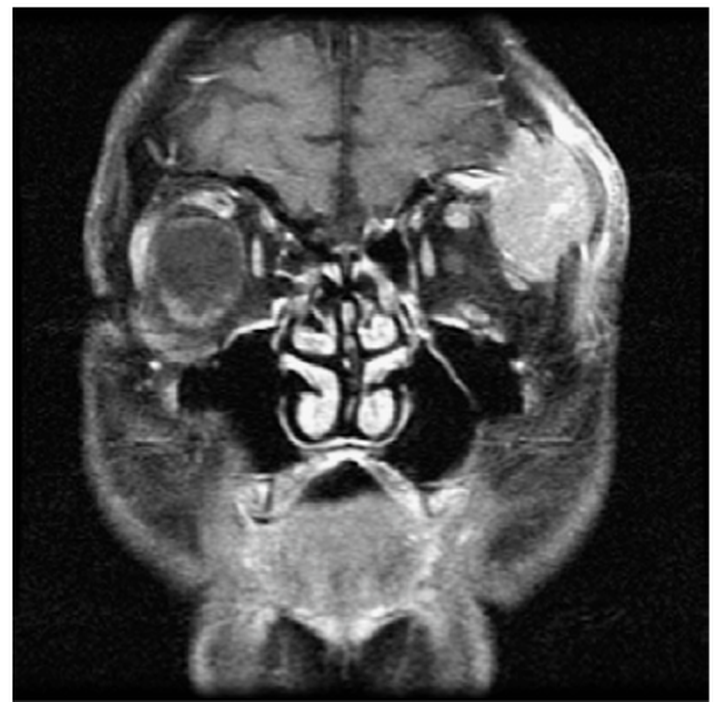

眼眶综合征以眼眶或眶上疼痛、前额头痛、眼球突出、复视和视力模糊为特征。检查可见典型的眶周肿胀、压痛、明显的肿块和视力下降(图1)。

图1。冠状位,对比增强后,T1加权MRI,72岁男性有严重疼痛和进行性突眼。眼眶切除及游离瓣重建均顺利,导致疼痛明显减轻。该肿瘤较初被认为是原发性泪腺癌,但较终被发现来自小的原发性肺癌,被肺纤维化所掩盖。